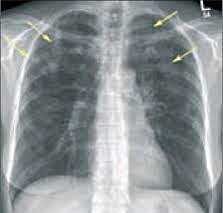

На рентгенограммах и КТ определяются участки инфильтрации различной плотности, расположенные по периферии, как правило, в верхних долях лёгких. В анализах крови выявляются значительное увеличение общего IgE, воспалительные изменения: повышение СОЭ, С-реактивного белка. Эозинофилия в крови определяется не всегда, но в БАЛ превышает 25%. В отличие от острой эозинофильной пневмонии длительность заболевания более 2 мес., возможны рецидивы.

- Рентгенография легких. На снимках видны субплеврально расположенные одиночные (реже множественные, двусторонние) нечеткие затемнения средней интенсивности неправильной формы размером до 3-4 см. В окружении инфильтрата легочный рисунок усилен, тень корня легкого слегка расширена. Характерна быстрая динамика инфильтратов с миграцией по легочным полям и исчезновением не позднее 1-2 недель после обнаружения (чаще через 1-3 дня) без остаточной рубцовой деформации. При длительно поддерживающемся инфильтративном воспалении в ткани легких могут образоваться фиброзные очаги и кистозные полости.

- Рентгенологические исследования. Одним из наиболее информативных методов диагностики легочных эозинофилий считается рентгенография грудной клетки. На снимках обнаруживаются летучие (мигрирующие) эозинофильные инфильтраты в виде участков затемнения. При аллергическом бронхолегочном аспергиллезе могут быть видны бронхоэктазы, фиброз верхних отделов легких.